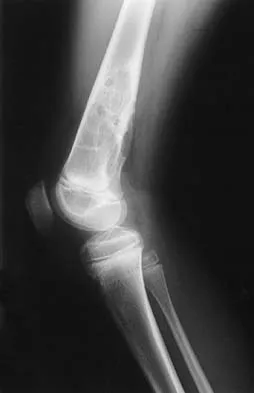

Figures 12a and 12b show the radiographs of a 50-year-old patient who reports acute knee pain after sustaining a twisting injury while playing tennis. Examination is unremarkable. The next most appropriate step in management should consist of

Explanation

The radiographs show localized diffuse cortical thickening that is characteristic of melorheostosis. The condition may be monostotic or it may involve many bones in one extremity (monomelic) in the distribution of a sclerotome. Bone scans will show increased uptake at the site or sites of skeletal involvement. Long tubular bones are most commonly involved. Melorheostosis is usually asymptomatic and requires no treatment. On rare occasions, there may be associated soft-tissue contractures. Dorfman H, Czerniak B: Bone Tumors. St Louis, MO, Mosby Inc, 1998, pp 1105-1107. Campbell CJ, Papademetriou T, Bonfiglio M: Melorheostosis: A report of the clinical, roentgenographic, and pathological findings in fourteen cases. J Bone Joint Surg Am 1968;50:1281-1304.